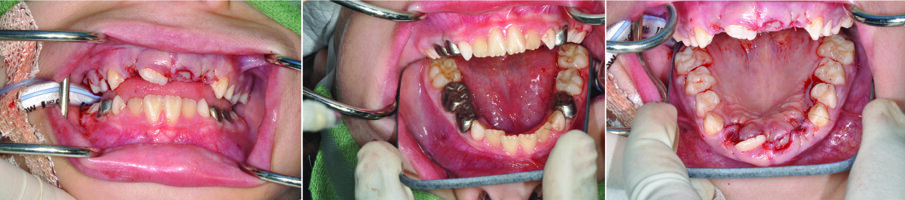

b) Surgical treatment

- After giving local anaesthesia, a continuous palatal intracrevicular (sulcular) incision was carried out from 54 to 64 (Fig. 5)

- Raised a mucoperiostial flap with the nasopalatine bundle exposed and preserved (Fig. 6)

- The palatal bone was exposed and a bulbosity was noted in the supernumerary ($) area. The overlying “egg shell” bone was removed with an osteotome. The $ was identified carefully as not to be confused with tooth 21 (Fig. 7)

- The $ tooth was elevated atraumatically as possible (Fig 8 a, b & c)

- The bone was filed and irrigated with saline and tooth 21 was incisally-exposed. A decision not the place a gold chain attachment on 21 was made as 21 was not covered with bone. (Fig. 9)

- The flap was repositioned and interrupted sutures were placed (resorbable sutures) after exposure of 21 with a small buccal apically repositioned flap (Fig. 10 a & b).

- Extraction of loose 52, 62

- A post surgical intra-operative assessment was carried out (Fig 11 a, b & c)

Figs. 8. (a, b & c) show sequence of careful elevation of the supernumerary ($) tooth.

Fig. 9. A survey of the surgical site after irrigation and bone filing was made.

Figs. 10 (a & b). Repositioned palatal flap and wound closure with resorbable sutures. Tooth 21 is now exposed after a small apically repositioned flap

Figs. 11 (a, b & c). Show the immediate post operative views